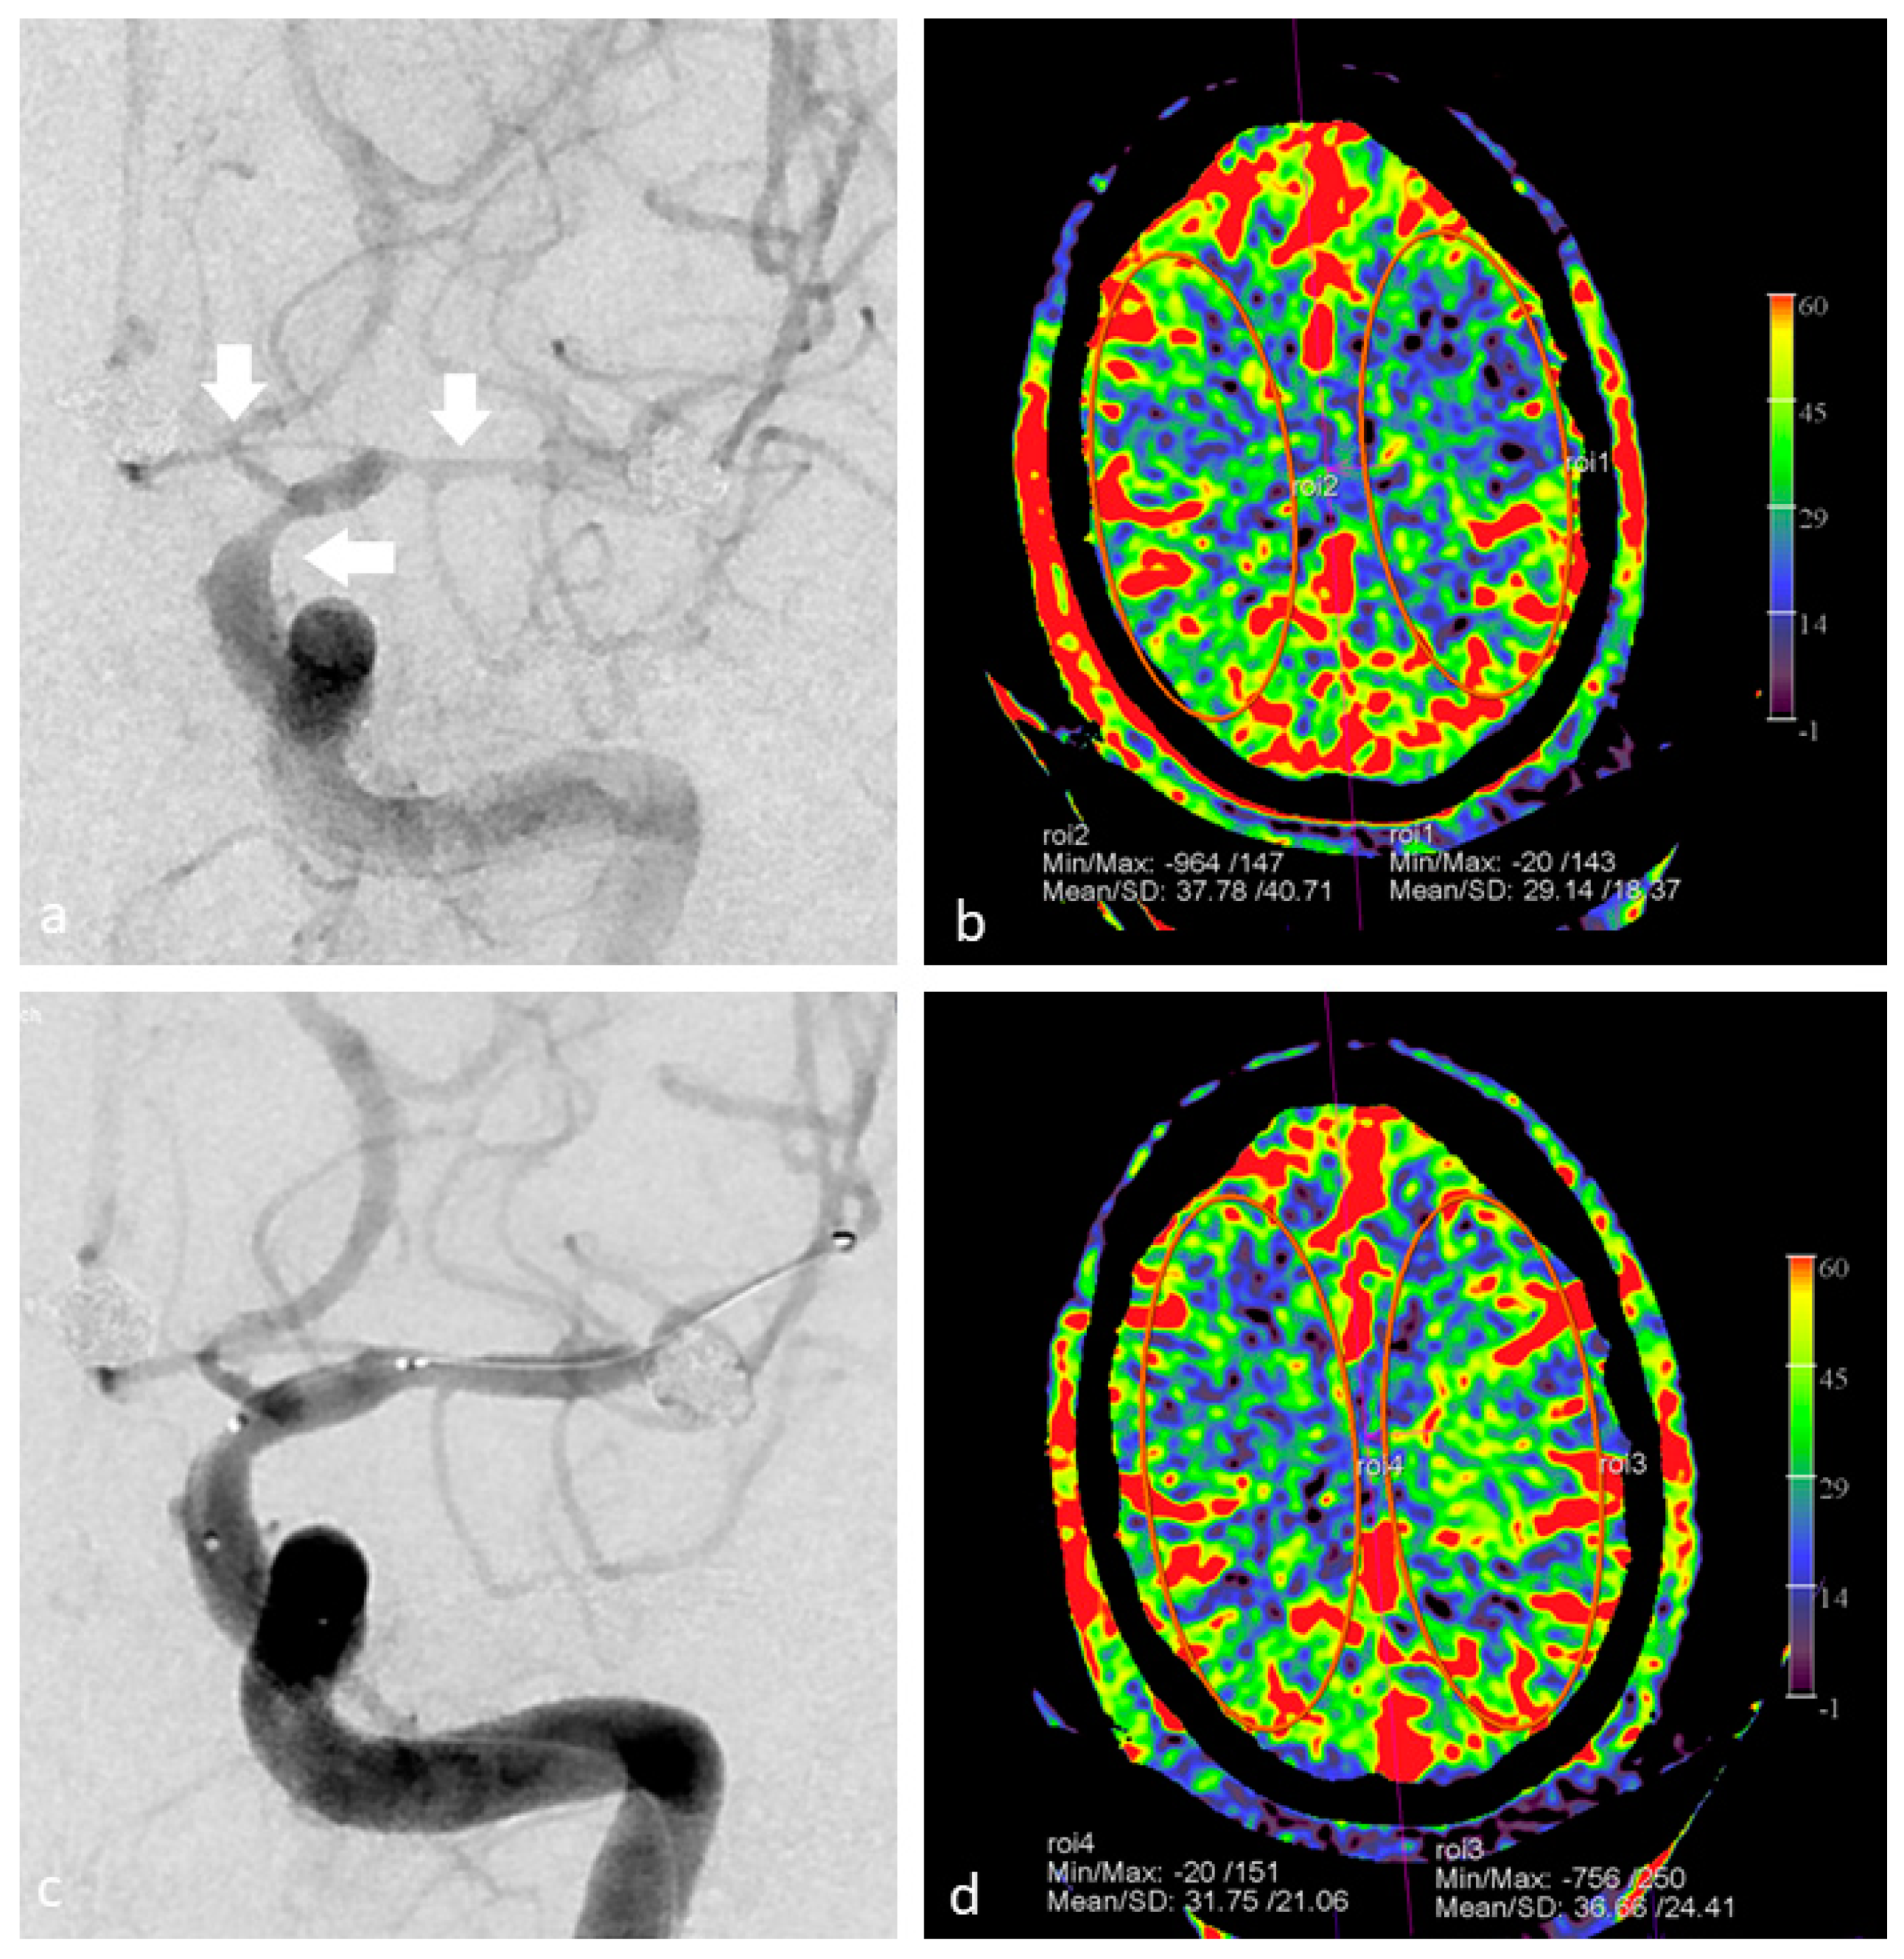

Recently, we documented the value of PBV imaging in a small group of patients after bypass and burr hole surgery [62]. Besides whole brain PBV imaging with the possibility of PBV mapping, we demonstrated the potential of PBV mapping by selective contrast injection in the bypass arteries. We were able to precisely delineate the effect of individual bypass arteries, or the efficacy of dural artery recruitment after burr hole surgery. In Figure 4, the use of FD CT PBV scanning with selective contrast injection besides whole brain FD CT PBV imaging is demonstrated in a moyamoya disease patient treated with bilateral multiple burr holes surgery.

Figure 4.

Selective and whole brain FD CT PBV imaging in a 29-year-old Asian male with moyamoya disease, treated by multiple burr holes surgery. Scanning was performed during aortic root injection (whole brain PBV imaging) and during selective ECA injection. (a) Coronal mask and PBV fusion MIP reformation demonstrates symmetrical PBV maps, and shows that multiple burr holes are present (white arrows). (b) Coronal PBV MIP reformation with selective right ECA contrast injection displays the blood supply to the right cerebral hemisphere (white arrows). (c) PBV value measurements in symmetrically plotted ellipsoid regions of interest (ROI) show symmetric PBV values.

In summary, FD CT PBV imaging by means of selective single artery contrast injection and whole brain contrast injection allows the evaluation of the impact of revascularization procedures in patients with chronic steno-occlusive disease both during the procedure and in long-term follow-up.